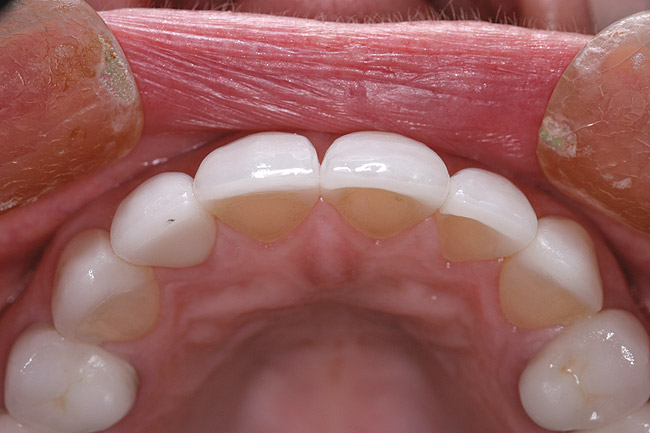

Figure 16 and Figure 17 An example of properly contoured anterior restorations. Notice the convex profile, natural drape of the lip, and point of interaction with the lower lip.

Figure 16

Figure 17

Determining the Horizontal Position of the Incisal Edge

Establishing the proper horizontal incisal edge position may be one of the most important, yet most commonly overlooked, factors in anterior reconstruction. This position must accommodate the patient’s envelope of function and neutral zone. A position too far to the facial can lead to interference as the lower lip closes to seal against the upper lip. A facialization error can also affect the function of the upper lip, causing the lip to have to “work around” the incisal edge. Many times the patient will complain of muscle fatigue and a “not quite right” feeling during function. A lingualization error of the incisal edge can lead to an anterio-posterior constriction in the patient’s envelope of function. This would occur as the edges interfere with the lower incisors’ arc of closure.3,12 Similarity exists with the vertical incisal edge position with regard to phonetic issues. A horizontal discrepancy can interfere with the production of “F” and “V” sounds. In addition, the horizontal edge position must accommodate production of the “S” sound. These sounds are created by the squeezing of air between the upper and lower incisors. Difficulty in creating this sound can be very frustrating for the patient.2,13 This author has found it to be more common to err with the edge position to the facial. This is usually caused by the preparation design error of under-reduction and failure to reduce anterior teeth in three planes. When the middle and incisal thirds are under-reduced, the laboratory technician has no choice but to fabricate an over-contoured restoration. Reduction stents can be produced from the diagnostic wax-up to aid in proper reduction depths (Figure 15). The final restorations should exhibit a three-plane convex contour as seen in natural teeth (Figure 16 and Figure 17).